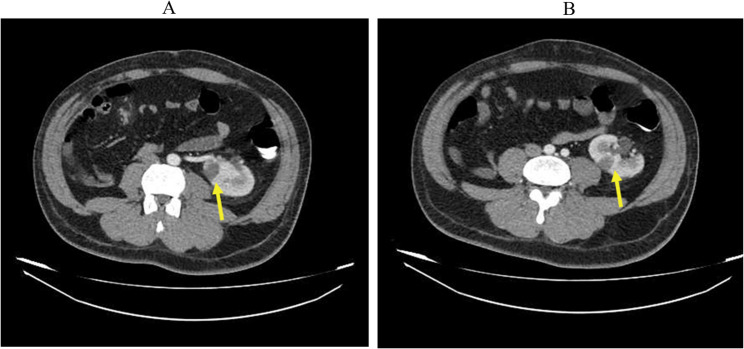

Case presentation: We report a rare case of a man with simultaneous spleen and left kidney infarction captured on contrast-enhanced computed tomographyeffects, without evidence of thrombosis or atherosclerosis, findings strongly suggestive of methamphetamine-induced vasospasm. The patient's abdominal pain improved under observation within days without apparent tissue loss or organ failure. Unfortunately, the patient passed away as a result of bradycardia and cardiac arrest.